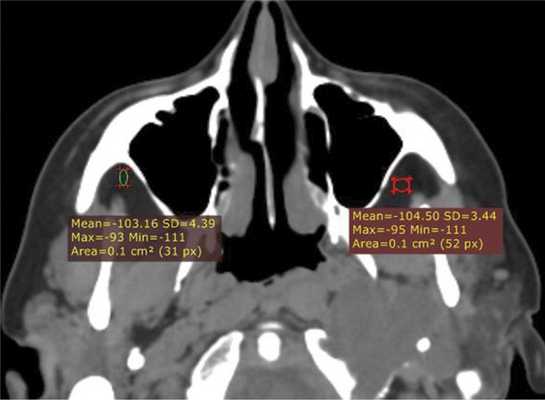

(Слева) При аксиальной «костной» КТ определяются классические признаки фиброзной дисплазии: выраженное вздутие левой верхнечелюстной пазухи с асимметричным выбуханием левой щеки, типичный вид «матового стекла». Обратите внимание на значительное уменьшение объема воздушной полости.

(Справа) При корональной костной КТ определяется фиброзная дисплазия с поражением правой нижней носовой раковины и латеральной стенки носа. Определяется выраженная экспансия раковины с изменениями в виде «матового стекла».

(Слева) При корональной «костной» КТ определяется экстенсивная фиброзная дисплазия орбит, петушиного гребня, решетчатой кости, среднего носового хода справа. Носовая перегородка отклонена влево.

(Справа) При аксиальной MPT Т2 в зоне фиброзной дисплазии определяется характерный выраженный гипоинтенсивный сигнал. Эти изменения типичны, когда наблюдаются совместно с «матовым стеклом» на КТ, и более диагностически значимы, чем гиперинтенсивные на Т2 очаги.